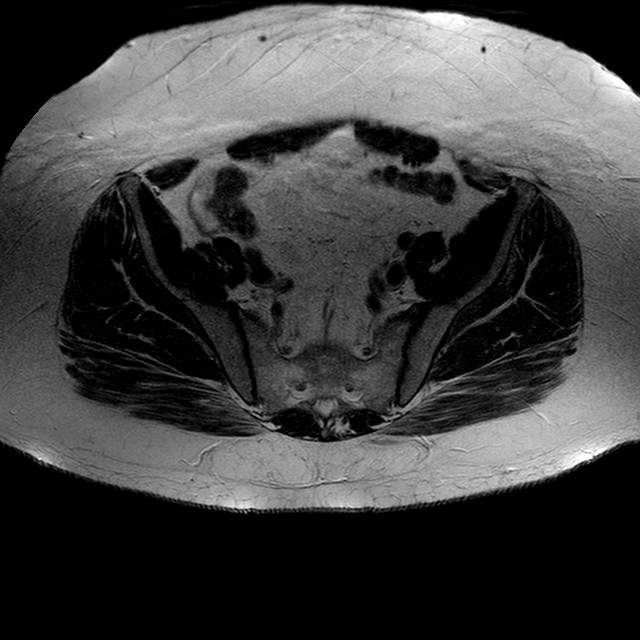

Esami: RMN BACINO

T2w TSE

Evidenti e simmetriche alterazioni osteofitosiche in regione coxo femorale con riduzione delle rime articolari. Degenerazione completa del cercine glenoideo. Non attuali segni di versamento articolare. Non segni di edema osseo che escludono attuale algodistrofia od osteonecrosi. Lieve e simmetrica riduzione del trofismo della muscolatura glutea.